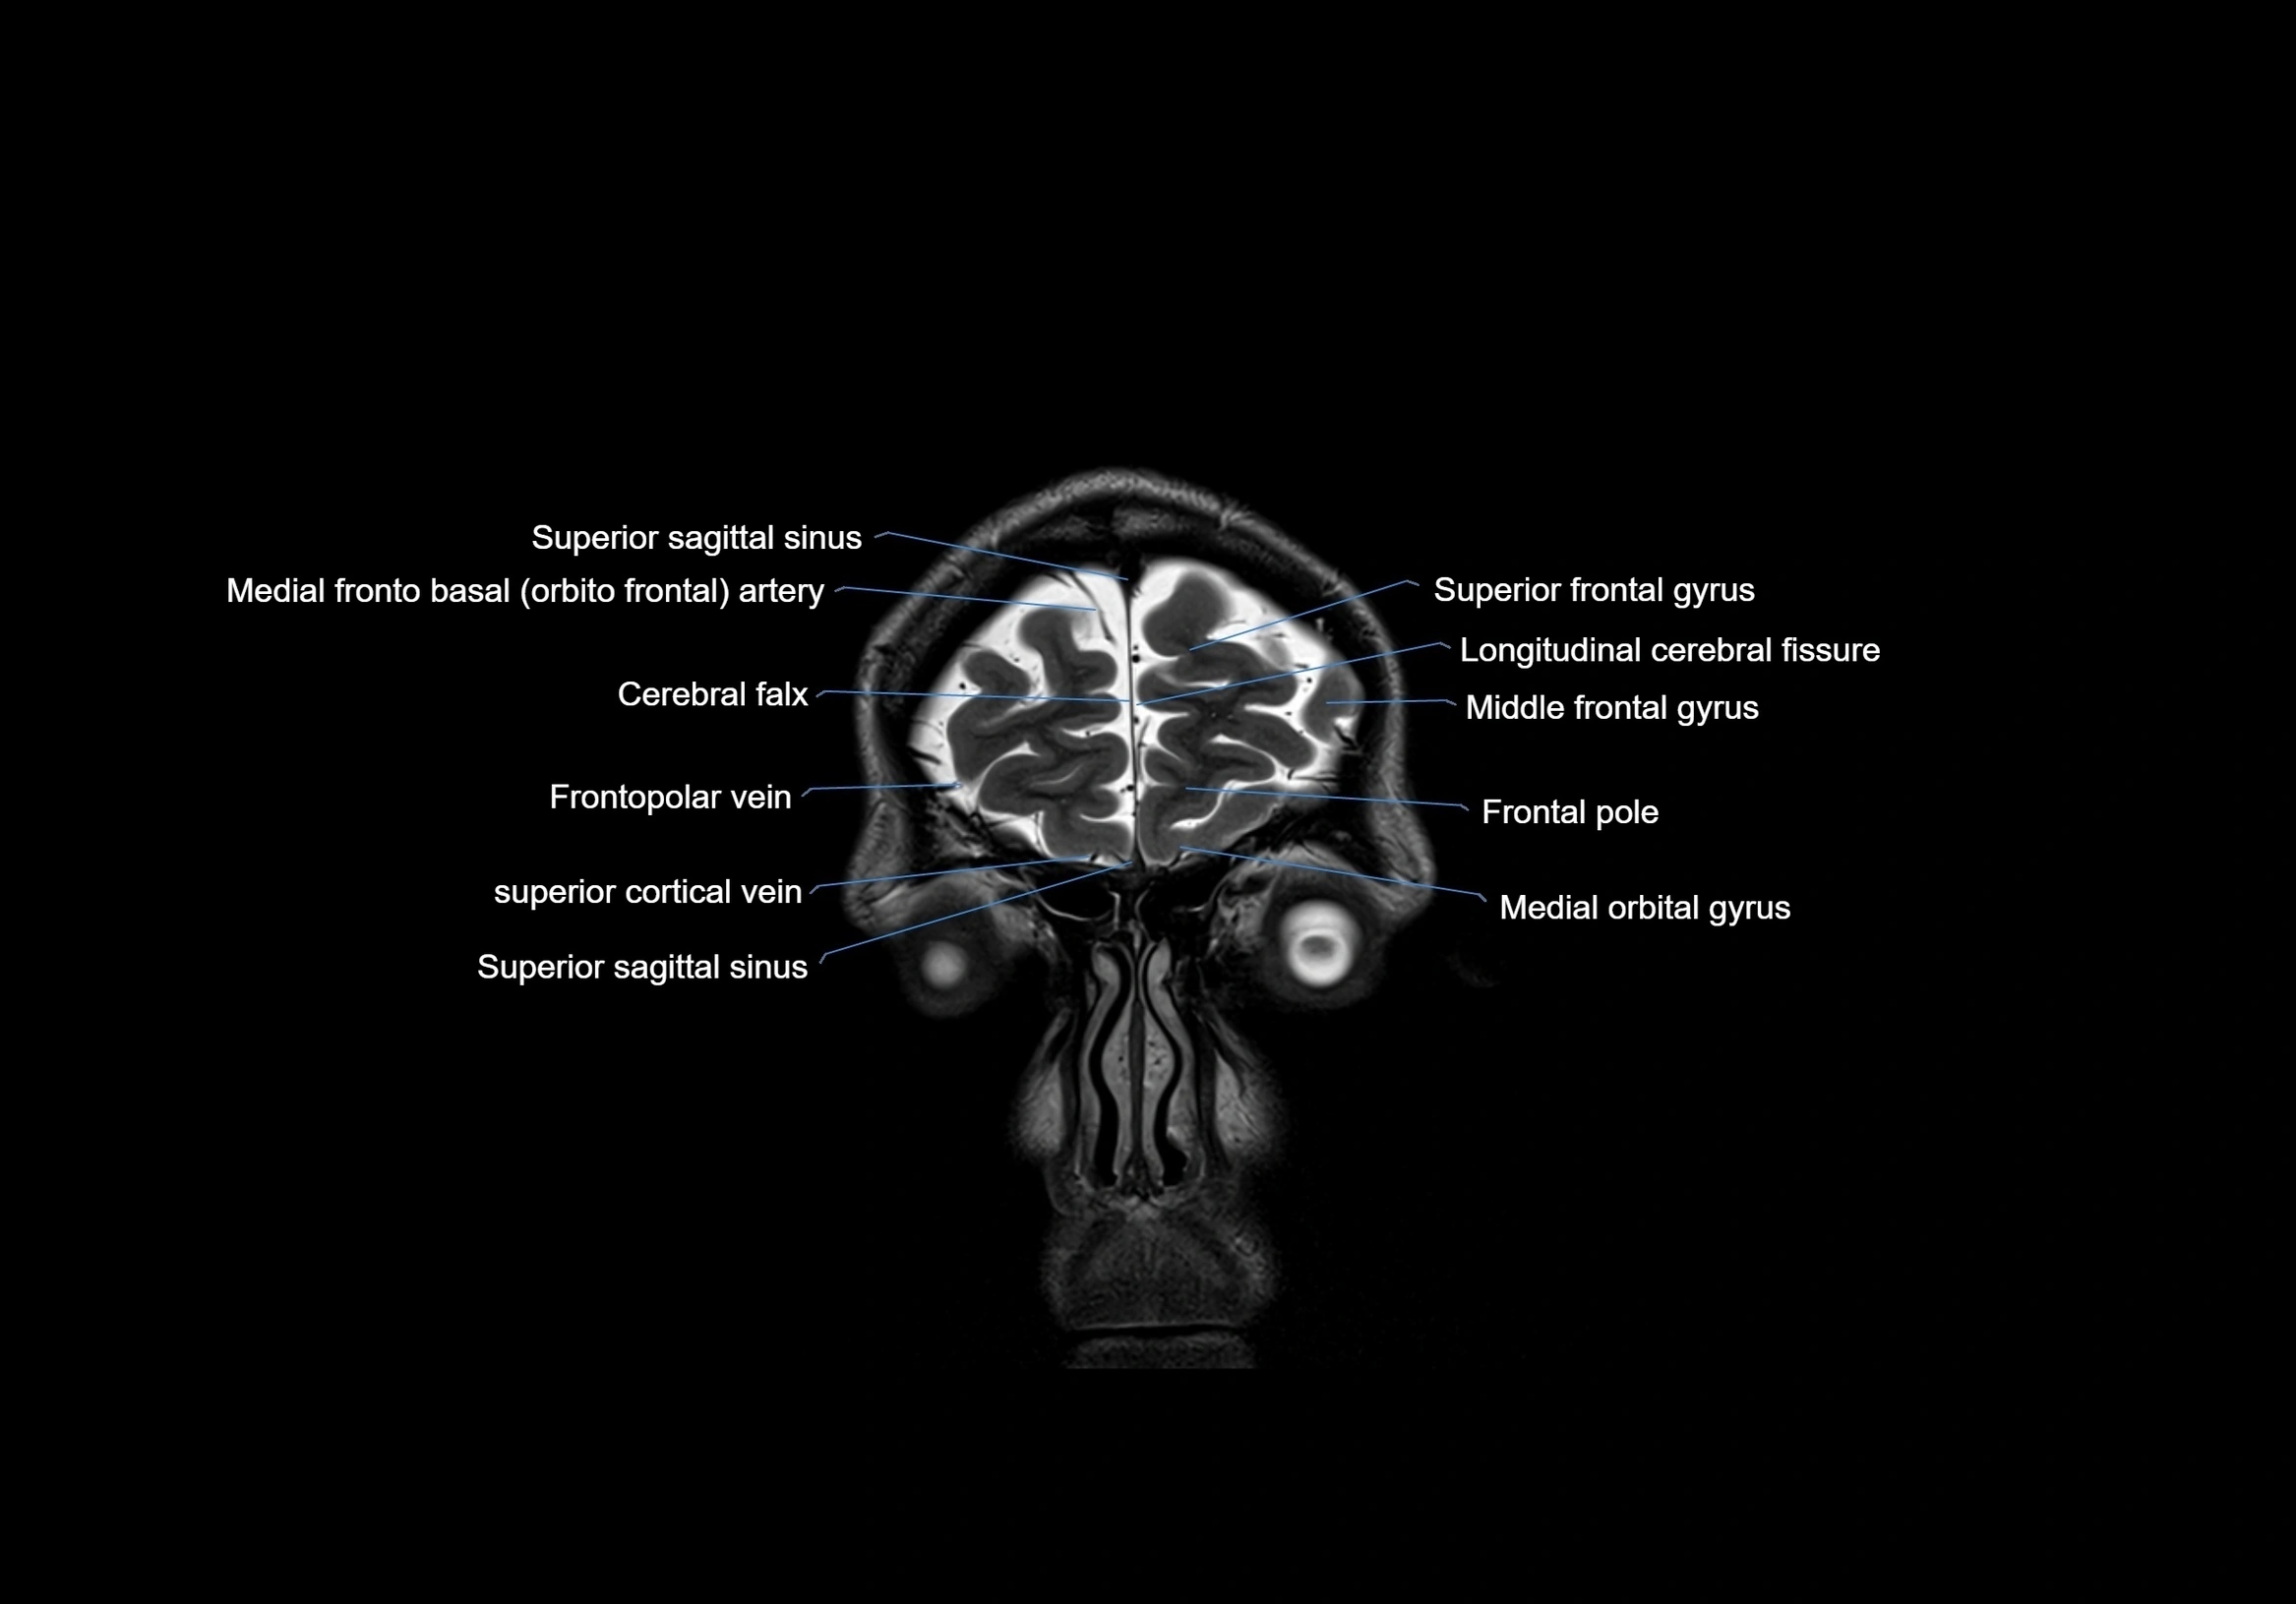

- Frontal pole

- Frontopolar vein

- Longitudinal cerebral fissure

- Medial frontobasal artery

- Medial orbital gyrus

- Middle frontal gyrus

- Superior frontal gyrus

- Superior sagittal sinus